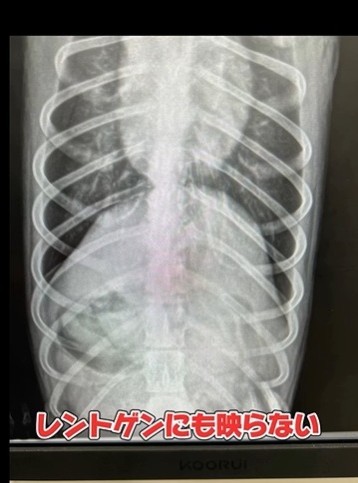

「串はレントゲンに映らないことが多く、吐かせるのも危険です。特に胃から腸へ移動する前に対応できるかが鍵になります」と稲野辺院長。今回のような誤飲事故は、実は多くの家庭で起こり得るもの。焼き鳥や串カツなど、香りや味が強い食べ物は、ペットにとっては“ごちそう”。目を離したすきに…ということも珍しくありません。